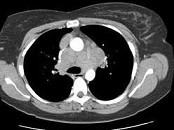

单项选择题女,33岁, 咳嗽,无发热, 结合图像,最可能的诊断是 ( )

A、肺结节病

B、淋巴瘤

C、中央型肺癌

D、胸腺瘤

E、支气管囊肿